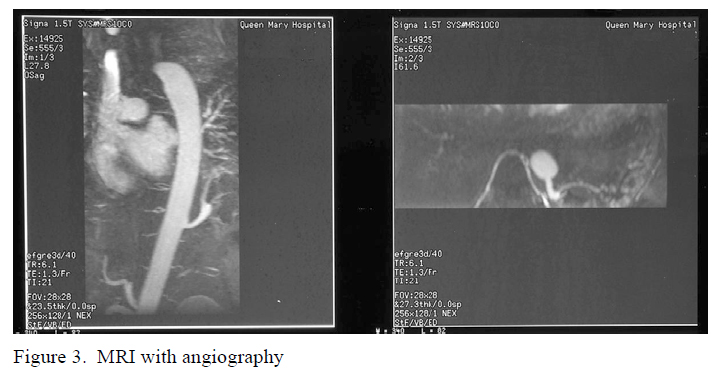

More advanced imaging study with 3–dimensional Magnetic Resonance Angiography (MRA) demonstrated the arterial supply from the descending thoracic aorta to the left lower lobe (figure 3)